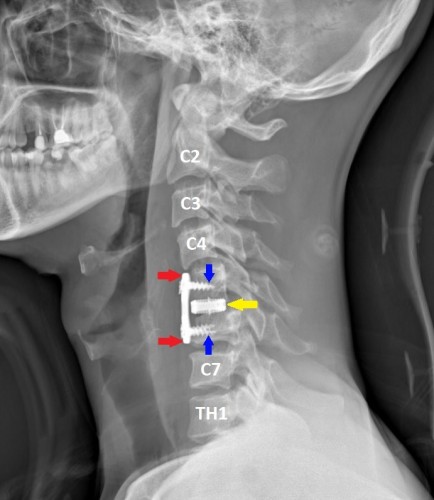

Заходя в оперблок, нейрохирурги уже знали, что будут делать. Под увеличением, с использованием операционного микроскопа, через небольшой разрез кожи по передне-боковой поверхности шеи была удалена травматическая грыжа диска. Затем, под рентген-контролем был успешно вправлен вывих, а позвонки зафиксированы при помощи титанового кейджа и пластины.

После операции – боковая проекция